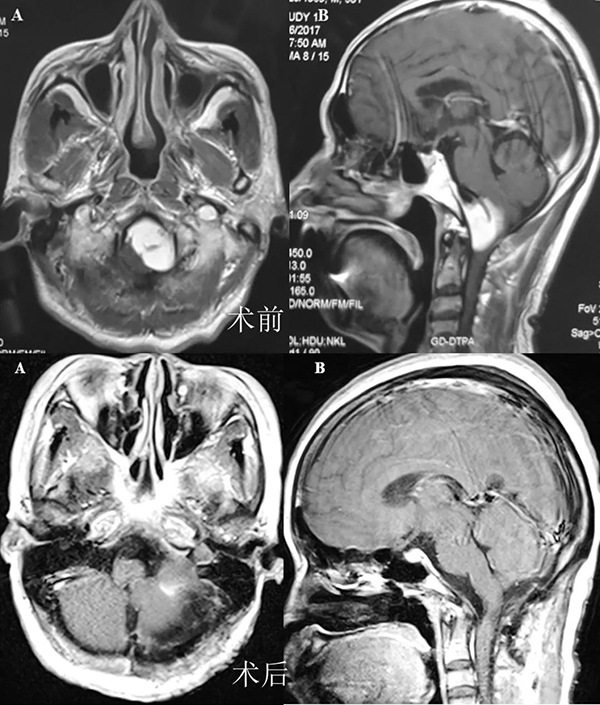

左侧颈静脉孔区神经鞘瘤手术前后

颅颈联合+经乳突经颈静脉突入路